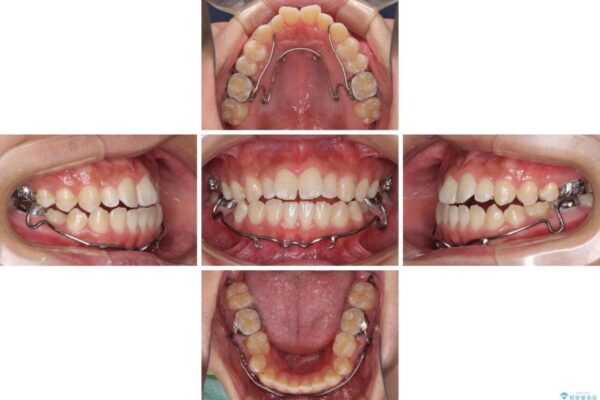

治療途中

• 口元の突出感を改善 受け口傾向の咬み合わせの抜歯矯正 治療途中画像